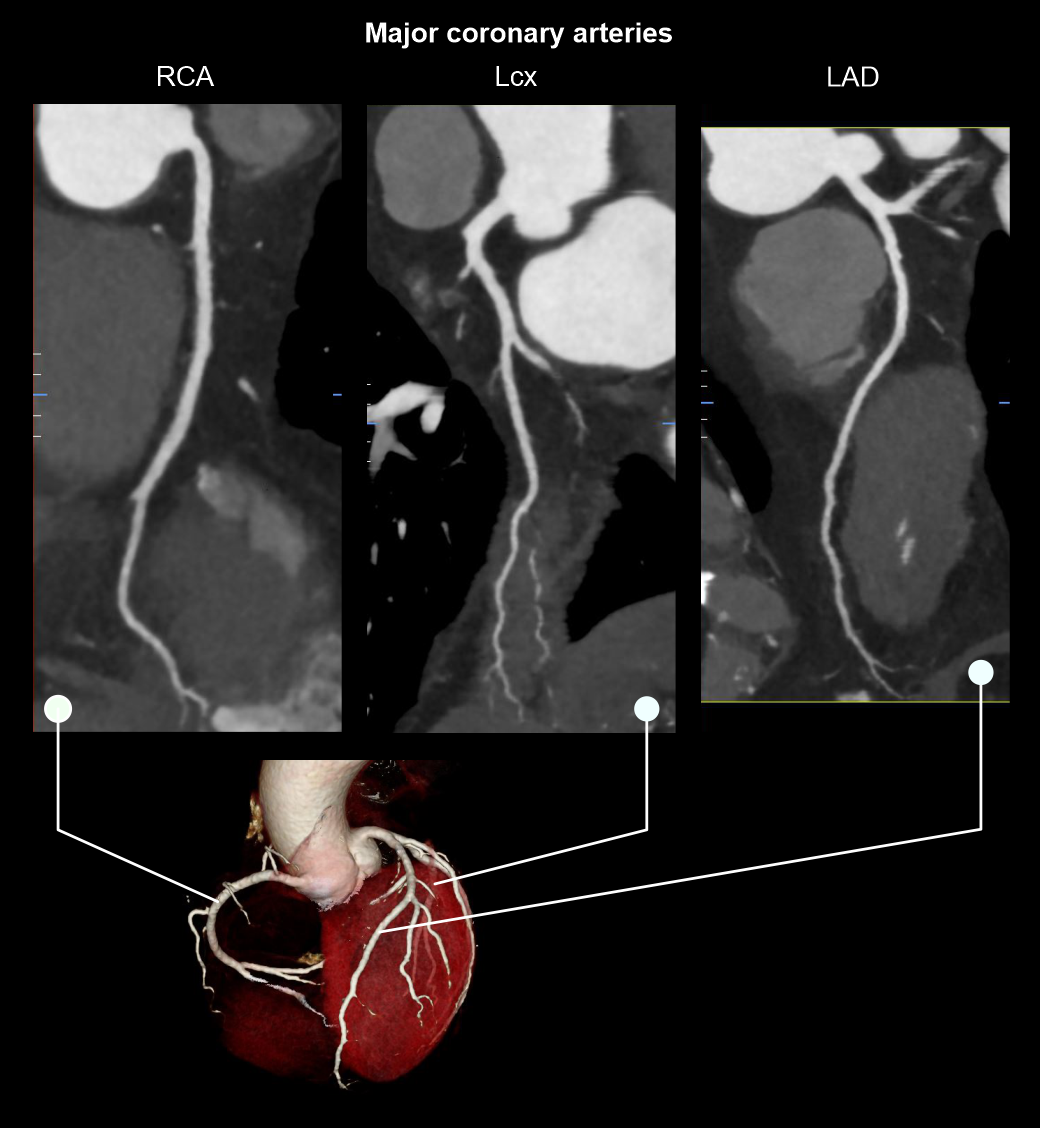

- Curved planner reformations (CPRs) of coronary arteries.

- 3D reconstructed and maximum intensity projection images.